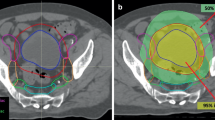

Stereotactic radiotherapy

For synchronous de novo oligometastatic patients, the metastatic site would be treated after treating the primary disease. Patients with extracranial metastases were treated with stereotactic body radiotherapy. Briefly, each patient received computerized tomography scan for planning purposes (P-CT) on a 16-slice CT scanner (Brilliance CT Big Bore Oncology, Philips Medical Systems, Inc., Cleveland, OH, USA) with vacuum cushions in breath-hold for thoracic or upper abdomen targets whenever possible. In cases where patients could not hold their breath, they underwent 4D P‑CT to delineate the moving target lesions with an additional abdominal compression being applied as passive motion management.

Patients with cranial metastases received stereotactic radiosurgery (SRS) or fractionated radiotherapy (SFR). Briefly, patients would receive histological confirmation, either by means of open surgery or stereotactic biopsy, followed by a P-CT for simulation in a stereotactic frame.

The radiation dose for SBRT/SRS/SFRT was prescribed to the isodose line (90–67%) to achieve dose-inhomogeneity in the center of the tumor [20]. The typical number of fractions would be 1–12, depending on the site, tumor size, and motion management. Lesions were counted separately if they had separate planning target volumes (PTV).

Thirty-one patients were identified in the local register with oligometastatic or recurrent head and neck tumors who received stereotactic radiotherapy throughout their treatment and met the inclusion criteria. The median prescribed dose was 45 Gy (range 60–24 Gy) with a median equivalent dose of 2 Gy per fraction (EQD2 α/β 10) = 88 Gy (range 93.8–31.2 Gy) and median three fractions (range 1–12 fractions).